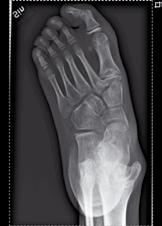

Figur 1a-d. Belastade fotbilder hos patient med bilateral spastisk cerebral pares med tydlig abduktion av framfoten på höger sida(fig 1a), där man på sidobilden (fig 1b) ser ett tydligt ”midfoot break” Patienten går med tåisättning på båda fötter och uppvisar tydlig hallux valgus bilateralt. Fig 1c visar peroperativa röntgenbilder, där laterala delen av foten förlängts genom insättning av strukturellt bengraft någon centimeter från leden mot cuboideum. Fig 1 d visar MTP I artrodes med stiftfixation på samma fot.

Ofta är spetsfotsställningen kombinerad med en adduktion eller abduktion av framfoten vilket vanligen brukar förklaras med muskulär ”obalans” eller ”överaktivitet”. Den muskulära obalansen ändras ofta med tiden, och en varus-adductusfot hos ett 4-5 årigt barn kan ett par år senare ha blivit en valgusfot, där framfoten istället kommit att svänga ut i abduktion (fig1a, 2a). Generellt tenderar valgusställning (eller snarare ökande framfotsabduktion) att tillta med ökande ålder under uppväxten och det är därför som en alltför tidig och ambitiös förflyttning av hela tibialis anteriorsenan lateralt lätt kan åstadkomma en överkorrektion.

och övriga framfoten glider på det rundade talushuvudet varvid mediala ligamentapparaten successivt blir alltmer uttänjd (fig 1) samtidigt som peroneusmuskulaturen bidrar till abduktionsställningen. Vanligen står inte hälarna inte så kraftigt i valgus inledningsvis, men detta kommer ofta med tiden. I och med att framfoten vid belastning pekar mer lateralt minskar plantarflexorernas möjlighet att hålla emot underbenets strävan framåt över foten, och risken för knäande gång ökar därvid ytterligare. Speciellt hos barn med sämre gångförmåga tillkommer med tiden också ofta en utåttorsion av underbenen och ibland även en valgusställning i själva talocruralleden. En idag vanlig operationsmetod, för att på barn med måttlig framfotsabduktion motverka naviculares lateralglidning på talus, är en förlängningsosteotomi på calcaneus 1-2 cm bakom calcaneocuboidleden. Efter att osteotomispalten bänts isär införes en kil av trikortikalt cristaben eller annat strukturellt bengraft (fig 1c, 2b). Är detta otillräckligt (som t.ex. vid samtidig ledlaxitet) kan foten stabiliseras ytterligare genom talonaviculär artrodes. För de mest felställda och rigida fötterna kan trippelartrodes bli aktuell.